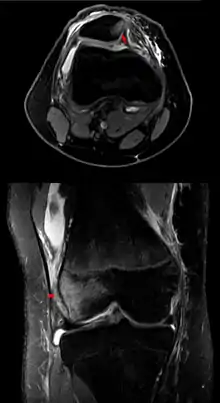

A luxating patella, sometimes called a trick knee, is a condition in which the patella, or kneecap, dislocates or moves out of its normal location.

Patellar luxation is a common condition in dogs, particularly small and miniature breeds. The condition usually becomes evident between the ages of 4 and 6 months. It can occur in cats, as well, especially domestic short-haired cats.[1]

It also occurs in humans, where it can be associated with damage to the anterior cruciate ligament.[2]

Diagnosis is made through palpation of the knee, to see whether it slips inside the joint more than would normally be expected. Often, a dog owner might be told that his or her pet has "loose knee", but this is not a medical term, and it is not correct to use it interchangeably with luxating patella.[4]

Luxating patella cannot be present without the knee being loose, but a loose knee is not necessarily slipping out of the joint. Even with luxating patella, symptoms such as intermittent limping in the rear leg might be mild or absent. Physical examination and manual manipulation are the preferred methods for diagnosis. More extreme cases can result in severe lameness. Osteoarthritis typically develops secondarily.[4]

The four recognized diagnostic grades of patellar luxation include, in order of severity:[4]

- Grade I - the patella can be manually luxated but is reduced (returns to the normal position) when released.

- Grade III - the patella remains luxated most of the time, but can be manually reduced with the stifle joint in extension. Flexion and extension of the stifle results again in luxation of the patella.

- Grade IV - the patella is permanently luxated and cannot be manually repositioned, with up to 90° of rotation of the proximal tibial plateau. The femoral trochlear groove is shallow or absent, with displacement of the quadriceps muscle group in the direction of luxation.